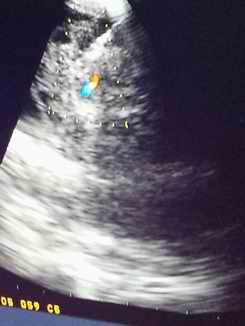

图片2超声定位肿大淋巴结